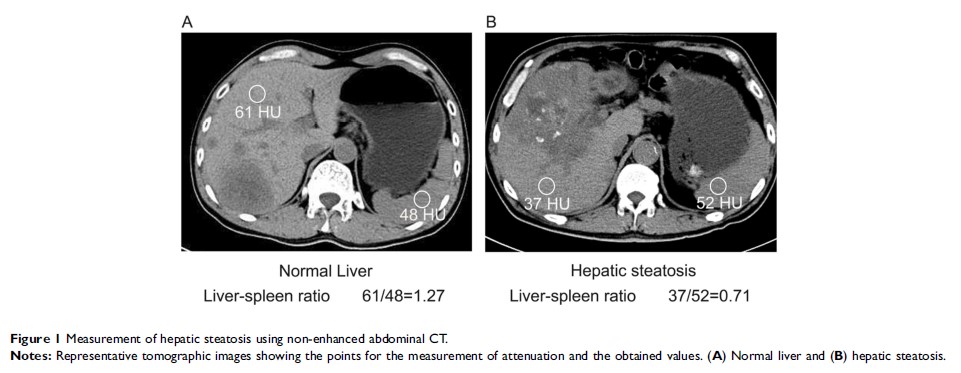

在大肠肝有限转移的转换治疗中肝脂肪变性的预测价值和预后价值:倾向评分匹配分析